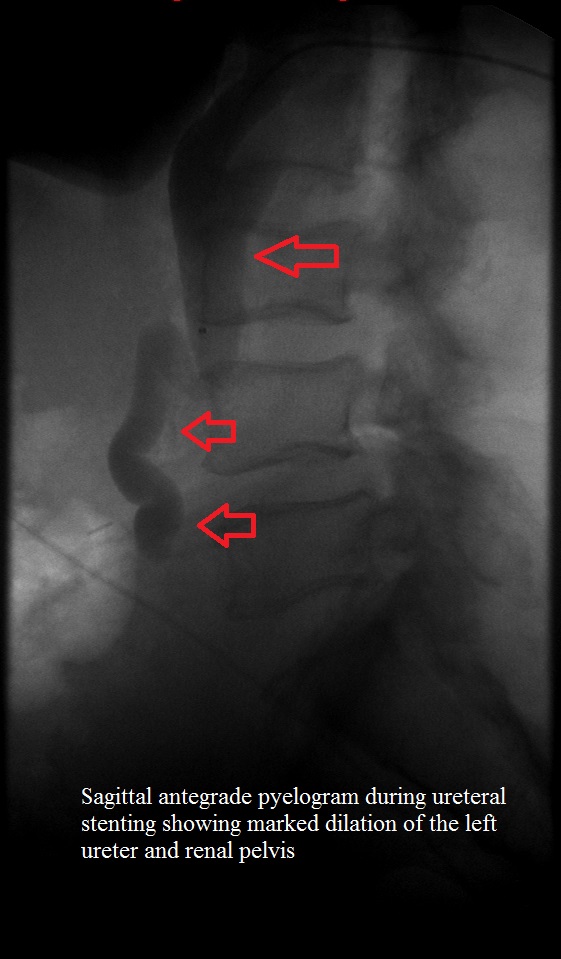

Lateral left antegrade pyelogram during stenting

Lateral fluoroscope early in left ureteral stenting showing dilated left ureter and renal pelvis.